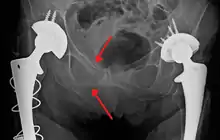

Blunt pelvic trauma

The most common causes of blunt pelvic trauma are motor vehicle accidents and multiple-story falls, and thus pelvic injuries are commonly associated with additional traumatic injuries in other locations.[28] In the pelvis specifically, the structures at risk include the pelvic bones, the proximal femur, major blood vessels such as the iliac arteries, the urinary tract, reproductive organs, and the rectum.[29][28]

.png.webp)

One of the primary concerns is the risk of pelvic fracture, which itself is associated with a myriad of complications including bleeding, damage to the urethra and bladder, and nerve damage.[30] If pelvic trauma is suspected, emergency medical services personnel may place a pelvic binder on patients to stabilize the patient's pelvis and prevent further damage to these structures while patients are transported to a hospital. During the evaluation of trauma patients in an emergency department, the stability of the pelvis is typically assessed by the healthcare provider to determine whether fracture may have occurred. Providers may then decide to order imaging such as an X-ray or CT scan to detect fractures; however, if there is concern for life-threatening bleeding, patients should receive an X-ray of the pelvis.[31] Following initial treatment of the patient, fractures may need to be treated surgically if significant, while some minor fractures may heal without requiring surgery.[28]

A life-threatening concern is hemorrhage, which may result from damage to the aorta, iliac arteries or veins in the pelvis. The majority of bleeding due to pelvic trauma is due to injury to the veins.[30] Fluid (often blood) may be detected in the pelvis via ultrasound during the FAST scan that is often performed following traumatic accidents. Should a patient appear hemodynamically unstable in the absence of obvious blood on the FAST scan, there may be concern for bleeding into the retroperitoneal space, known as retroperitoneal hematoma. Stopping the bleeding may require endovascular intervention or surgery, depending on the location and severity.[29]